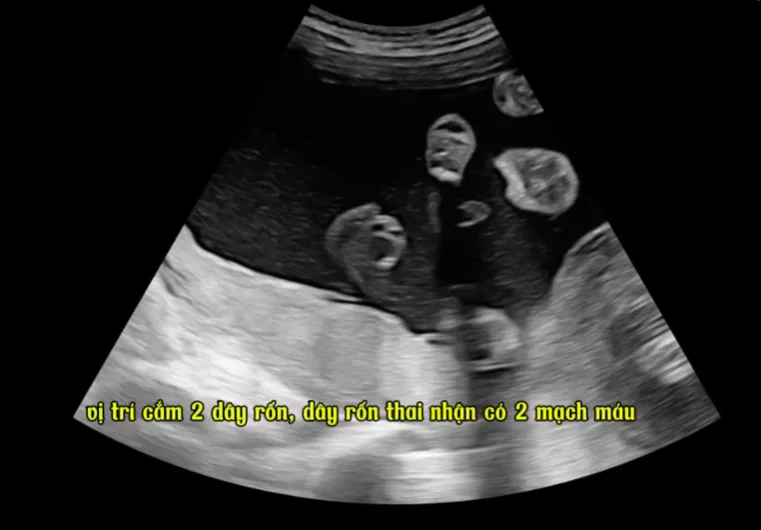

Dây rốn quấn nhau ở song thai (Cord entanglement)